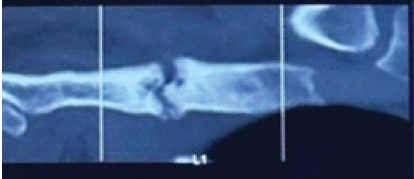

Modified Posterior Approach for Scapular Body Non-union: A Case Report

Deepak Kumar , Arjit Bansal , Sai Surya Dinesh Pydi , M Harshith , Kartik Sharma